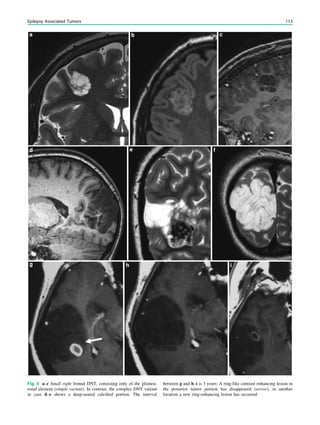

Fig. 1 Digital photogram of the brain surface before placement of a

subdural 8 9 8 grid. A second photogram was taken after grid

placement and digitally replaced by a schematic drawing detailing the

results of electrical stimulations and ictal/ intraictal EEG activity. Blue

grid contacts represent the eloquent zone, which is the motor cortex in

this case. The black area represents the epileptogenic lesion, defined

as the radiographic lesion that causes the seizures. The yellow area is

the seizure onset zone, defined as the area from which the clinical

seizures are generated. The seizure onset zone is often, but not

necessarily, congruent with the epileptogenic zone, defined as the

cortex area indispensable for the generation of seizures